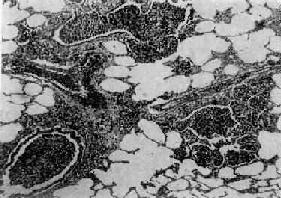

图9-17 肺肉质变 肺泡腔内炎性渗出物已被结缔组织所替代 (2)肺脓肿及脓胸或脓气胸:多见于由金黄色葡萄球菌引起的肺炎。 (3)纤维素性胸膜炎:是肺内炎症直接侵犯胸膜的结果。 (4)败血症或脓毒败血症:见于严重感染时,细菌侵入血流繁殖所致。 (5)感染性休克:严重的肺炎链球菌或金黄色葡萄球菌感染引起严重的毒血症时可发生休克,称休克型或中毒性肺炎,病死率较高。 【临床病理联系】 疾病发展过程中病变表现不一,临床体征也不相同。疾病早期时,主要病变是肺泡腔内浆液渗出,听诊可闻湿啰音,X线检查仅见肺纹理增深。肺实变时,由于肺泡膜面积减少,可出现肺泡通气和血流比例失调而影响换气功能,使肺静脉血不能充分氧合,患者乃出现紫绀或呼吸困难。渗出物中红细胞为肺泡巨噬细胞吞噬,崩解后形成含铁血黄素混入痰中,使痰呈铁锈色。痰中可检出“心衰细胞”。肺实变的体征是,肺泡呼吸音减弱或消失,出现支气管呼吸音,语音震颤增强,叩诊呈浊音。因常并发纤维素性胸膜炎,患者有胸痛,听诊可闻胸膜摩擦音。X线检查,可见大叶性或段性分布的均匀性密度增高阴影。病变消散时,渗出物溶解液化,肺部可闻及捻发音,X线表现为散在不均匀片状阴影,约在2~3周后阴影方完全消散。抗生素治疗,可缩短病程,减轻病变,合并症也大为减少。 2.小叶性肺炎 小叶性肺炎(lobular pneumonia)主要由化脓菌感染引起,病变起始于细支气管,并向周围或末梢肺组织发展,形成以肺小叶为单位、呈灶状散布的肺化脓性炎。因其病变以支气管为中心故又称支气管肺炎(bronchopneumonia)。主要发生于小儿和年老体弱者。 【病因和发病机制】 小叶性肺炎主要由细菌感染引起,常见的致病菌有葡萄球菌、链球菌、肺炎球菌、流感嗜血杆菌、绿脓杆菌和大肠杆菌等。这些细菌通常是口腔或上呼吸道内致病力较弱的常驻寄生菌,往往在某些诱因影响下,如患传染病、营养不良、恶病质、慢性心力衰竭、昏迷、麻醉、手术后等,使机体抵抗力下降,呼吸系统的防御功能受损,细菌得以入侵、繁殖,发挥致病作用,引起支气管肺炎。因此,支气管肺炎常是某些疾病的并发症,如所谓麻疹后肺炎、手术后肺炎、吸入性肺炎、坠积性肺炎等等。 【病理变化】 小叶性肺炎的病变特征是肺组织内散布一些以细支气管为中心的化脓性炎症病灶。常散布于两肺各叶,尤以背侧和下叶病灶较多。病灶大小不等,直径多在1cm左右(相当于肺小叶范围),形状不规则,色暗红或带黄色(图9-18)。严重者,病灶互相融合甚或累及全叶,形成融合性支气管肺炎(confluent bronchopneumonia)。镜下,病灶中支气管、细支气及其周围的肺泡腔内流满脓性渗出物,纤维蛋白一般较少(图9-19)。病灶周围肺组织充血,可有浆液渗出、肺泡过度扩张等变化。由于病变发展阶段的不同,各病灶的病变表现和严重程度亦不一致。有些病灶完全化脓,支气管和肺组织遭破坏,而另一些病灶内则可仅见浆液性渗出,有的还停留于细支气管及其周围炎阶段。

图9-19 支气管肺炎 图中见灶状实变的肺组织,肺泡内充满以中性粒细胞为主的炎性渗出物;病灶中有发炎的细支气管 【并发症】 小叶性肺炎发生并发症的危险性比大叶性肺炎大得多。可并发心力衰竭、呼吸衰竭、脓毒败血症、肺脓肿及脓胸等。支气管破坏较重且病程较长者,可导致支气管扩张。 【临床病理联系】 因小叶性肺炎多为其他疾病的并发症,其临床症状常为原发性疾病所掩盖。由于支气管粘膜的炎症刺激而引起咳嗽,痰呈粘液脓性。因病变常呈灶性散布,肺实变体征一般不明显。病变区细支管和肺泡内含有渗出物,听诊可闻湿啰音。X线检查,可见肺野内散在不规则小片状或斑点状模糊阴影。本病发现及时,治疗得当,肺内渗出物可完全吸收而痊愈。但在幼儿,年老体弱者,特别是并发于其他严重疾病时,预后大多不良。 (二)病毒性肺炎 病毒性肺炎(viral pneumonia)常常是因上呼吸道病毒感染向下蔓延所致。患者多为儿童,症状轻、重不等,但婴幼儿和老年患者病情较重。一般多为散发,偶可酿成流行。引起肺炎的病毒种类较多,常见的是流感病毒、还有呼吸道合胞病毒、腺病毒、副流感病毒、麻疹病毒、巨细胞病毒等等,也可由一种以上病毒混合感染并可继发细菌感染。病毒性肺炎的病情、病变类型及其严重程度常有很大差别。 【病理变化】 早期或轻型病毒性肺炎表现为间质性肺炎,炎症从支气管、细支气管开始,沿肺间质发展,支气管、细支气管壁及其周围、小叶间隔以及肺泡壁等肺间质充血、水肿,有一些淋巴细胞和单核细胞浸润,肺泡壁明显增宽(图9-20)。肺泡腔内一般无渗出物或仅有少量浆液。病变较重者,肺泡也可受累,出现由浆液、少量纤维蛋白、红细胞及巨噬细胞组成的炎性渗出物,甚至可发生组织坏死。有些病毒性肺炎(如流感病毒肺炎,麻疹病毒肺炎、腺病毒肺炎等)肺泡腔内渗出较明显,渗出物浓缩凝结成一层红染的膜样物贴附于肺泡内表面,即透明膜形成。支气管上皮的肺泡上皮也可增生,甚至形成多核巨细胞。麻疹病毒肺炎的病变特点为在间质性肺炎的基础上,肺泡壁上有透明膜形成,并有较多的多核巨细胞(巨细胞肺炎),在增生的上皮细胞和多核巨细胞的胞浆内和胞核内可检见病毒包含体。病毒包含体常呈球形,约红细胞大小,呈嗜酸性染色,均质或细颗粒状,其周围常有一清晰的透明晕。其他一些病毒性肺炎也可在增生的支气管上皮、支气管粘液腺上皮或肺泡上皮细胞内检见病毒包含体。如腺病毒肺炎可在增生的上皮细胞核内(图9-21),呼吸道合胞病毒肺炎可在增生的上皮细胞胞浆内,巨细胞病毒肺炎也可在增生的上皮细胞核内检见病毒包含体。检见包含体是病理组织学诊断病毒性肺炎的重要依据。